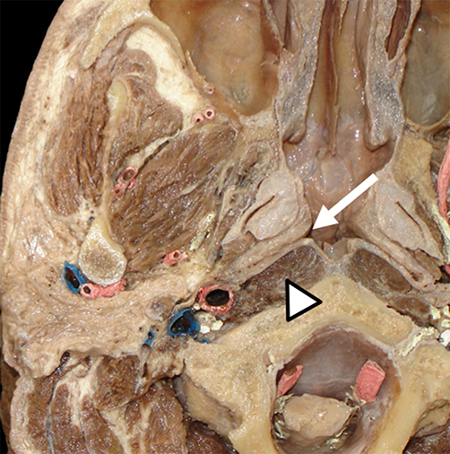

Preparado anatómico con tinciones de arterias en rojo y venas en azul. Se señala a la fosa de Rosenmüller derecha (flecha), ubicada inmediatamente por delante del músculo largo del cuello (cabeza de flecha).

Corte axial de resonancia magnética (RM) en imágenes ponderadas en T2. Paciente que consultó por sensación de oído derecho tapado e hipoacusia. Se observó una lesión que ocupaba y obstruía la fosa de Rosenmüller derecha (flecha) asociada a otitis serosa homolateral (cabeza de flecha). La lesión correspondió a un carcinoma escamoso de nasofaringe.